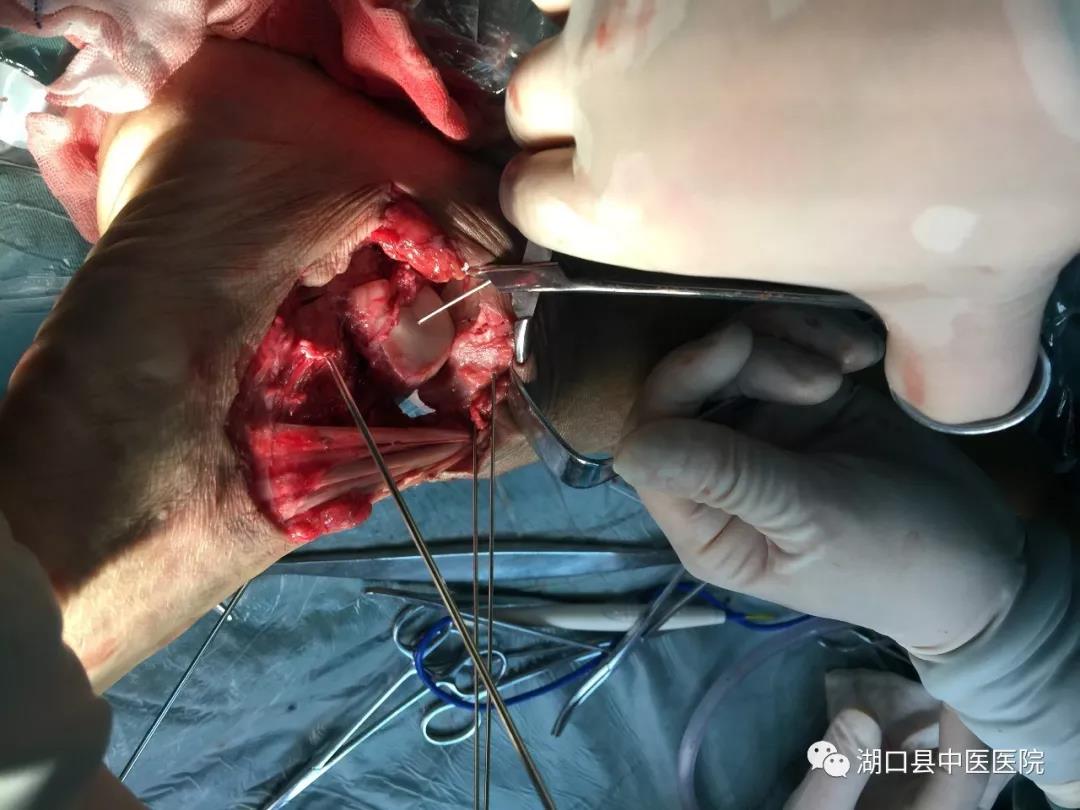

时间回到今年1月4日。晚间10时左右,刚做了2台急诊手术正准备休息的吴学峰医师接到急诊电话,有一名严重车祸伤患者,右下肢伤势严重,请求会诊。吴医生放下电话,急忙赶到急诊科。现场一看,患者周大叔伤情非常严重,右小腿被碾压得血肉模糊,受伤部位骨头外露,面色苍白,烦躁不安。血压80/50mmHg,肢体远端冰凉干瘪,摸不到血管搏动。病情之棘手超乎想象:一是伤者右下肢系车轮重物碾压后不全离断,皮肤软组织损毁严重、部分缺失,胫骨中下段、距骨、跟骨粉碎性骨折伴踝关节脱位;二是血管神经肌腱碾压离断,血管缺损;三是伤处沾满泥沙,污染严重。面对这些不利情况,通常来说进行截肢手术是最为稳妥的办法:手术难度低、过程短、风险小、费用低、后期并发症少。

按照预定计划,手术有条不紊地进行着,骨折的外固定支架临时固定,在显微镜下进行血管、神经的逐一吻合,肌腱的修复……经过6个多小时的持续作战,次日凌晨5时许,周大叔离断的下肢逐渐恢复红润,断肢再植术完成,手术成功。在骨伤科医护团队的密切配合和不懈努力下,经过抗凝、解痉、抗感染等治疗措施,右小腿血运良好,一期肢体成活。在周大叔住院期间,骨科专家柯阳春院长始终惦念着他的病情,经常来到病房看望了解情况。二期周大叔由于外伤导致踝关节周围皮肤缺损,胫骨及肌腱外露同时伴有感染,传统的植皮方法无法解决问题。骨伤科团队在柯院长主持下经过讨论后,决定应用显微外科技术吻合血管的游离股前外侧皮瓣修复创面,周大叔得以顺利康复出院。经了解,此例游离皮瓣修复创面为湖口县首例。